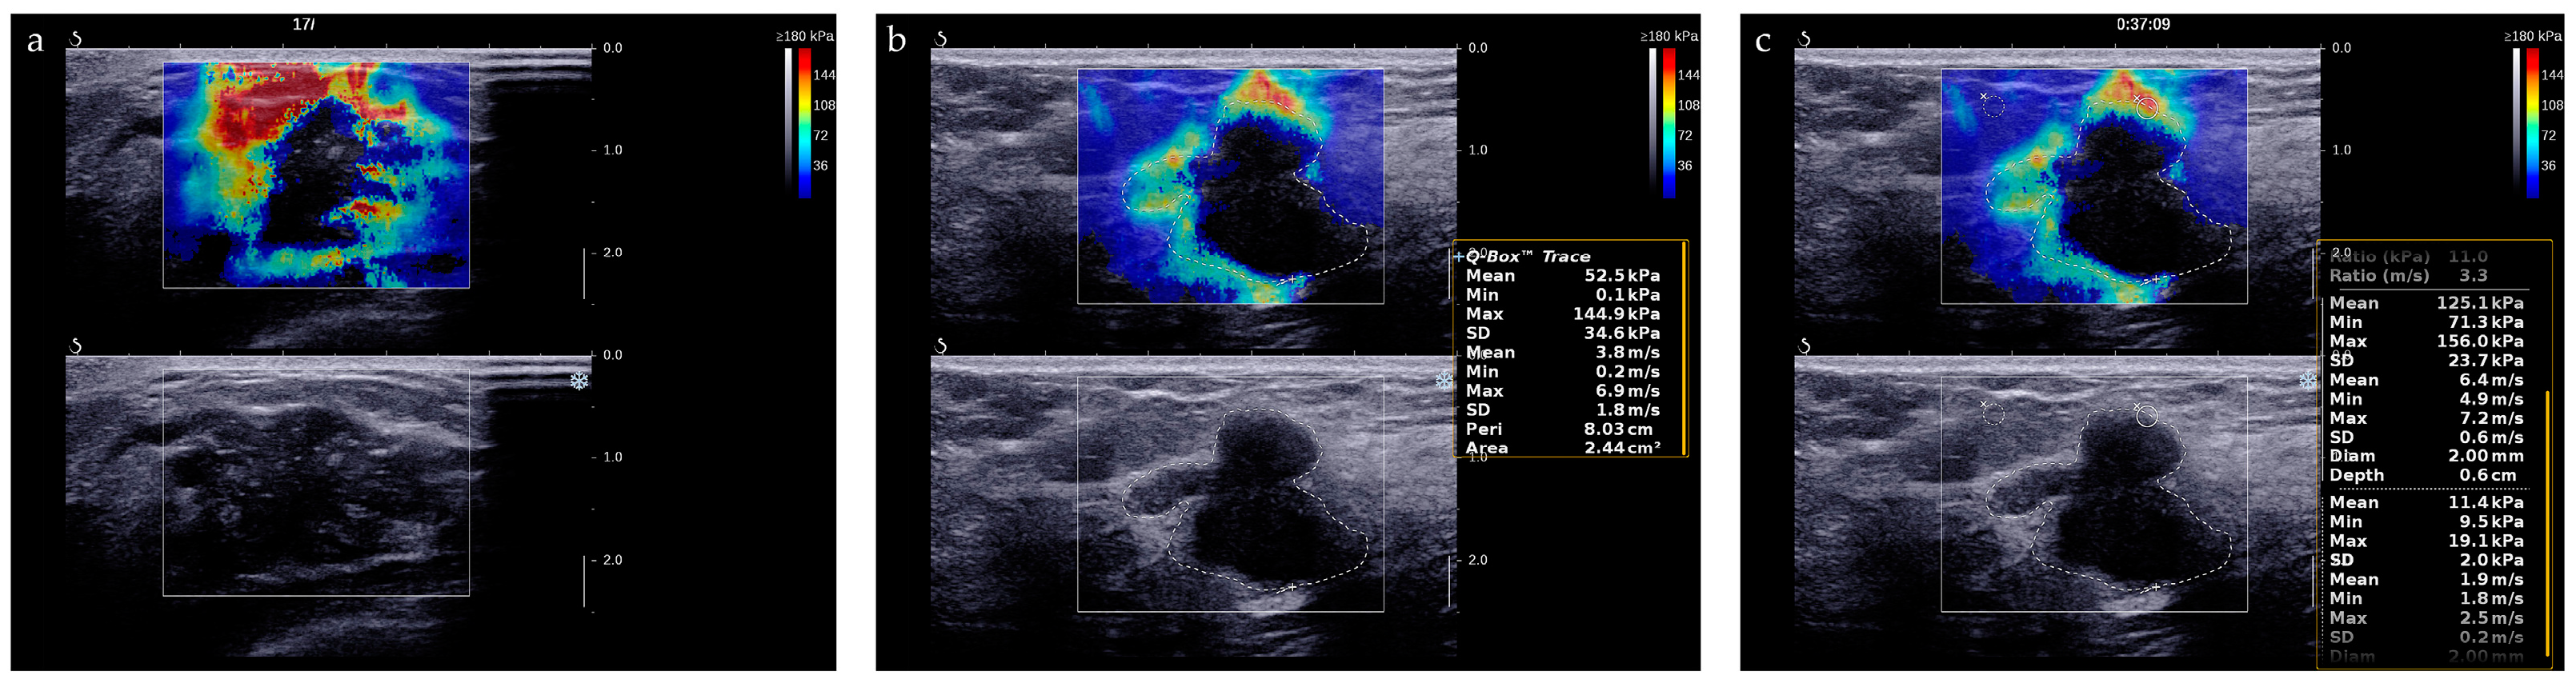

2.2. Ultrasound Image Acquisition

2.3. Ultrasound Image Evaluation

Appendix A. Detailed Descriptions of Shear Wave Elastography Parameters